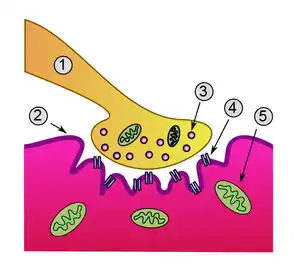

Neuromuscular junction. Lambert–Eaton myasthenic syndrome is caused by autoantibodies to the presynaptic membrane. Myasthenia gravis is caused by autoantibodies to the postsynaptic acetylcholine receptors.

In normal neuromuscular function, a nerve impulse is carried down the axon (the long projection of a nerve cell) from the spinal cord. At the nerve ending in the neuromuscular junction, where the impulse is transferred to the muscle cell, the nerve impulse leads to the opening of voltage-gated calcium channels (VGCC), the influx of calcium ions into the nerve terminal, and the calcium-dependent triggering of synaptic vesicle fusion with plasma membrane. These synaptic vesicles contain acetylcholine, which is released into the synaptic cleft and stimulates the acetylcholine receptors on the muscle. The muscle then contracts.[4]

In LEMS, antibodies against VGCC, particularly the P/Q-type VGCC, decrease the amount of calcium that can enter the nerve ending, hence less acetylcholine can be released from the neuromuscular junction. Apart from skeletal muscle, the autonomic nervous system also requires acetylcholine neurotransmission; this explains the occurrence of autonomic symptoms in LEMS.[4][5] P/Q voltage-gated calcium channels are also found in the cerebellum, explaining why some experience problems with coordination.[6][7] The antibodies bind particularly to the part of the receptor known as the "domain III S5–S6 linker peptide".[7] Antibodies may also bind other VGCCs.[7] Some have antibodies that bind synaptotagmin, the protein sensor for calcium-regulated vesicle fusion.[7] Many people with LEMS, both with and without VGCC antibodies, have detectable antibodies against the M1 subtype of the acetylcholine receptor; their presence may participate in a lack of compensation for the weak calcium influx.[7]

Apart from the decreased calcium influx, a disruption of active zone vesicle release sites also occurs, which may also be antibody-dependent, since people with LEMS have antibodies to components of these active zones (including voltage-dependent calcium channels). Together, these abnormalities lead to the decrease in muscle contractility. Repeated stimuli over a period of about 10 seconds eventually lead to sufficient delivery of calcium, and an increase in muscle contraction to normal levels, which can be demonstrated using an electrodiagnostic medicine study called needle electromyography by increasing amplitude of repeated compound muscle action potentials.[4]